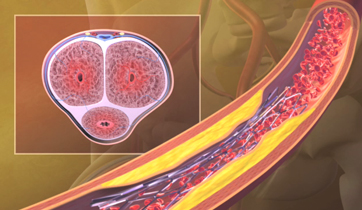

Erectile Dysfunction

Medtronic Corporation

This animationis intended to explain Erectile Dysfunction to physicians. It shows the vessels and nerves involved in blood flow obstruction to the penis, and the erectile tissue's failure to enlarge. The animation also suggests the benefits of clearing the obstruction by using stents.